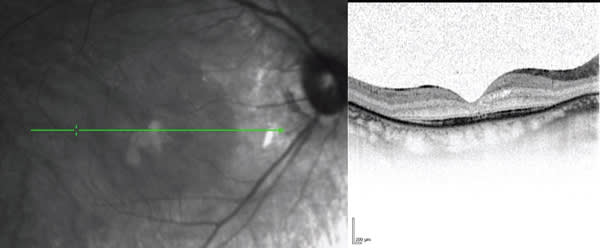

3. It is important to examine the entire set of OCT images of a lesion. During the treatment of AMD, it is not uncommon to find that intraretinal cysts or subretinal fluid are limited to just a few scans. The detection of these lesions is important to making optimal treatment decisions (Figure 1).

Figure 1. Spectral-domain optical coherence tomography has become the preferred method of assessing treatment responses in AMD.